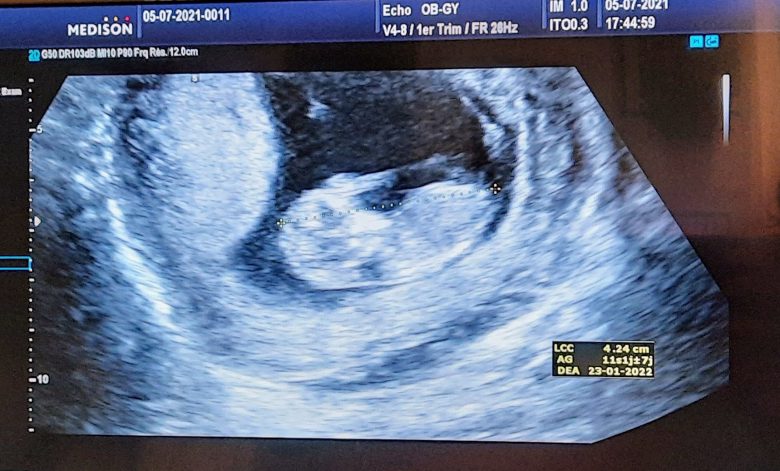

The following day, six weeks into the pregnancy, I had a first look at my baby. I heard the heartbeat for the first time and confirmed it was in the right place, inside the uterus, on the ER ultrasound machine. All was fine. The urine test came back normal 🙂 I got this one ultrasound image that I showed my husband who was waiting for me outside. He had not been allowed to accompany me in the ER because of COVID-19 restrictions. What a relief! And what a surprise to hear the baby’s heartbeat so early on! I had not expected that. It was so alert..

I had a medical check-up roughly once per month. Not counting the ER ultrasound, I saw the doctor at 7 weeks and then at 12 weeks. Blood pressure checked; cervix checked to make sure it was tightly shut; ultrasound to check the embryo/foetus. We heard the heartbeat every time. Luckily, despite the COVID-19 restrictions, pregnant ladies could be accompanied, so my husband came along to all the appointments. We had made it to the end of the first trimester. All was in order. We were happy.

My gynae called it a “miracle pregnancy”. Might be because of the little odds he had given me for conceiving naturally with one sub-optimal fallopian tube and a history of ectopic pregnancy, at my age. Might also be because the ultrasound showed that my right ovary (the side missing the fallopian tube) produced the lucky ovule, which was subsequently caught by the left fallopian tube.